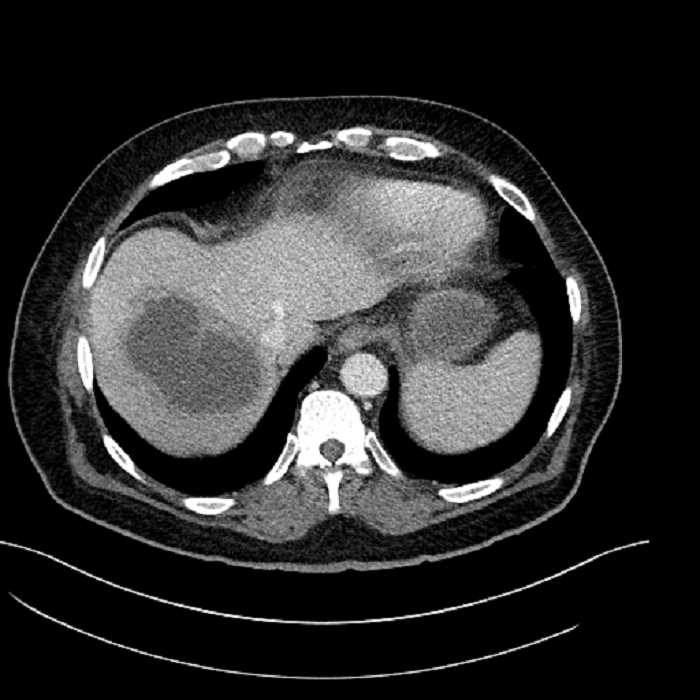

• Large fluid density structure in hepatic segments 7 and 8 measuring 10 x 7 x 7 cm with internal septation and circumferential ill-defined low density compatible with edema

• Peripherally enhancing subcapsular collections along the anterior margin of the left hepatic lobe measuring 3 x 1 cm and 2 x 1 cm

• Clearly marginated fluid density structure in segment 7 and several other scattered tiny hypodensities, which likely represent cysts

• Hepatic abscess

Acute sigmoid diverticulitis complicated by a small contained perforation and a large abscess in the right hepatic lobe. Additional small subcapsular abscesses along the anterior margin of the left hepatic lobe.

• The classic CT imaging appearance is a double target sign with internal low density surrounded by an internal enhancing rim (capsule) and a low density external rim (edema)

Hepatic abscess showing the double target sign with low density internally surrounded by a thin inner enhancing rim (red arrow) and ill-defined outer low density rim (yellow arrow). Blue arrow indicates an internal septation. Red arrows: additional smaller subcapsular abscesses. Red arrow: focal contained perforation associated with diverticulitis.